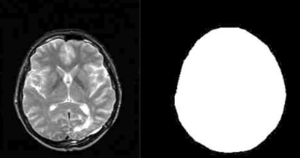

MRI-Only Based Radiotherapy Treatment Planning for the Rat Brain on a Small Animal Radiation Research Platform (SARRP)

Publication: PLoS One. 2015 Dec 3;10(12):e0143821. PMID: 26633302 | PDF Authors: Gutierrez S, Descamps B, Vanhove C. Institution: Medical Image and Signal Processing Group, Ghent University-iMinds Medical IT department, Ghent, Belgium. Background/Purpose: Computed tomography (CT) is the standard imaging modality in radiation therapy treatment planning (RTP). However, magnetic resonance (MR) imaging provides superior soft tissue contrast, increasing the precision of target volume selection. We present MR-only based RTP for a rat brain on a small animal radiation research platform (SARRP) using probabilistic voxel classification with multiple MR sequences. Six rat heads were imaged, each with one CT and five MR sequences. The MR sequences were: T1-weighted, T2-weighted, zero-echo time (ZTE), and two ultra-short echo time sequences with 20 μs (UTE1) and 2 ms (UTE2) echo times. CT data were manually segmented into air, soft tissue, and bone to obtain the RTP reference. Bias field corrected MR images were automatically segmented into the same tissue classes using a fuzzy c-means segmentation algorithm with multiple images as input. Similarities between segmented CT and automatic segmented MR (ASMR) images were evaluated using Dice coefficient. Three ASMR images with high similarity index were used for further RTP. Three beam arrangements were investigated. Dose distributions were compared by analysing dose volume histograms. The highest Dice coefficients were obtained for the ZTE-UTE2 combination and for the T1-UTE1-T2 combination when ZTE was unavailable. Both combinations, along with UTE1-UTE2, often used to generate ASMR images, were used for further RTP. Using 1 beam, MR based RTP underestimated the dose to be delivered to the target (range: 1.4%-7.6%). When more complex beam configurations were used, the calculated dose using the ZTE-UTE2 combination was the most accurate, with 0.7% deviation from CT, compared to 0.8% for T1-UTE1-T2 and 1.7% for UTE1-UTE2. The presented MR-only based workflow for RTP on a SARRP enables both accurate organ delineation and dose calculations using multiple MR sequences. This method can be useful in longitudinal studies where CT's cumulative radiation dose might contribute to the total dose. |

Illustration of a CB-CT and five MR images of the same animal. a) Coronal CB-CT image and (b)-(f) biased field corrected and masked coronal MR images using a T1-weighted (b), T2-weighted (c), ZTE (d), UTE1 (e) and UTE2 (f) sequence. All CB-CT images were first co-registered using 3D Slicer version 3.6.3 by rigid body transformations using normalized mutual information. |